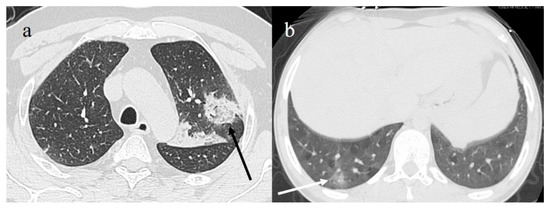

- Brogna, B.; Bignardi, E.; Salvatore, P.; Alberigo, M.; Brogna, C.; Megliola, A.; Fontanella, G.; Mazza, E.M.; Musto, L. Unusual presentations of COVID-19 pneumonia on CT scans with spontaneous pneumomediastinum and loculated pneumothorax: A report of two cases and a review of the literature. Heart Lung 2020, 49, 864–868. [Google Scholar] [CrossRef]

| Chest CT | In ED in presence of high pretest probability for symptomatic patients with comorbidities or functional impairment and during FU for patients at moderate–high risk of progression; evaluation of fibrotic changes complications (barotrauma, SPM, SPX, ARDS, TE); CT can be indicated for symptomatic patients with multiple negative RT-PCR results; long-term FU | Easily available, rapid, high sensitivity in early phase of COVID-19 pneumonia, prognostic and predictive value in mortality through evaluation of pneumonia extension with CT-SS index; possible to visualize Macklin effect on CT; post-mortem evaluation | Low specificity, high dose burden, not used for screening asymptomatic patients or those with mild symptoms |